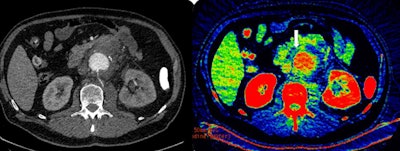

Sinitsyn's talk will in part focus on the use of dual-energy CT (DECT) for such emergency vascular cases. The technique increases conspicuity of iodine extravasation and intravascular thrombi, and the radiologist often can skip nonenhanced scans and perform only a single contrast-enhanced acquisition with reconstruction of virtual noncontrast images.

"DECT can yield qualitative information similar to MRI and reveal small quantities of iodine in tiny blood leaks in the soft tissue. There is no difference for the patient in terms of time, compared to nonenhanced scans, but it is only available on new generation scanners, less than 1% of all existing CT machines," he noted. "Given that the life span of a machine is eight to 10 years, it will be another decade before we can expect to see DECT routinely applied in acute abdominal emergencies."

In vascular abdominal emergencies, dual-phase (arterial and venous) low-dose enhanced CT, followed by fast review to decide if extra imaging is necessary, remained the protocol of choice. Without enhancement, very small leaks are hard to detect, so biphasic enhanced CT is a "must" for these tiny leaks and thrombosis. Using DECT, a single arterial-phase CT may be sufficient, Sinitsyn added.

"Detecting bleeding is difficult within the bowel due to the radiological signs associated with presence of food. DECT can help to determine if the hyperdense content is due to iodine, calcium, or other types of material," Sinitsyn said.